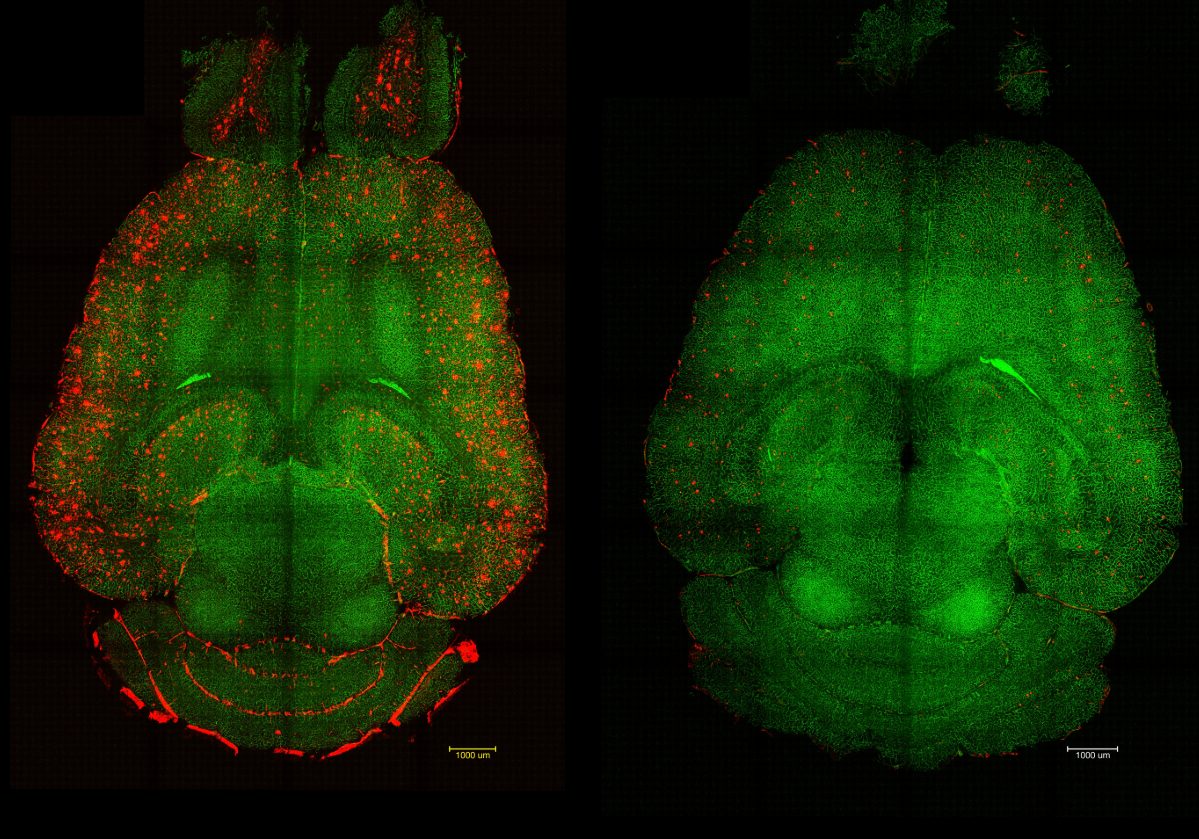

Ученые использовали наночастицы для восстановления функции гематоэнцефалического барьера, получив удивительные результаты. Буквально за 2 часа удалось очистить мозг мышей с прогрессирующей болезнью Альцгеймера от почти половины амелоидных бляшек.

В исследовании участвовали мыши возрастом около года, генетически модифицированные для развития агрессивной формы, схожей с болезнью Альцгеймера. Мыши были старыми, а их мозг был покрыт бета-амилоидными белками, вызывая значительные когнитивные нарушения. Буквально через 2 часа после единственного укола концентрация бета-амилоидов в мозге мышей снизилась почти на 45%.

Концентрация бета-амилоидов снижалась не только в мозге, но и в плазме крови. Это свидетельствовало о том, что токсичные белки из мозга попадали в организм для утилизации. Количество бета-амилоида, выведенного из мозга, практически полностью соответствовало его избытку в крови. Результаты сохранялись через 6 месяцев после инъекции.